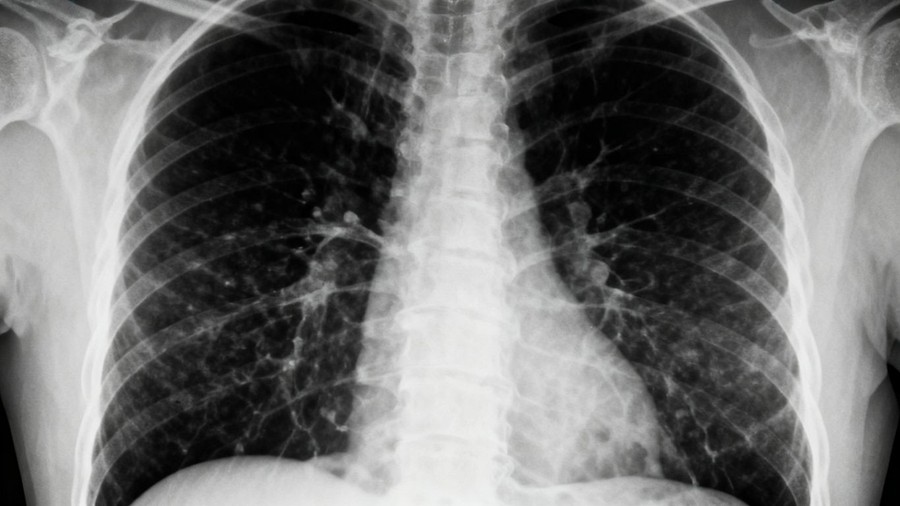

Asbestos Exposure and Lung Cancer Risk